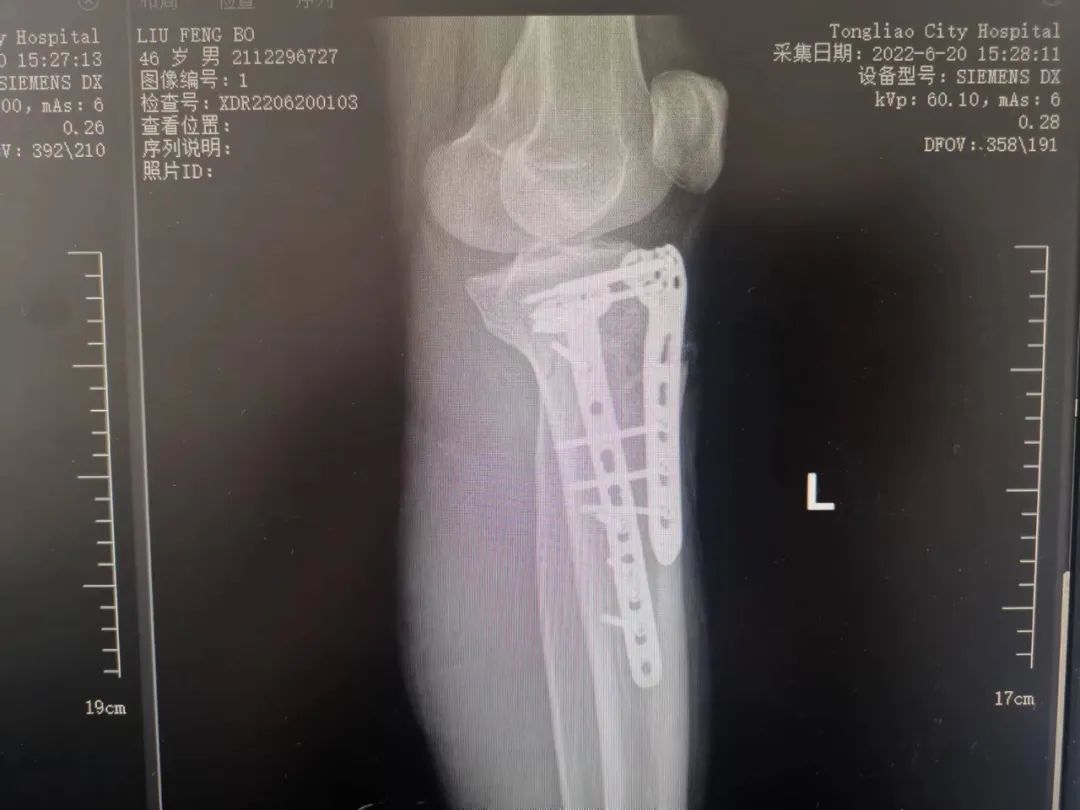

目前,复杂髋臼骨折的治疗仍然是骨科医生面临的最具挑战性的任务之一,随着创伤骨科的迅速发展,人们对创伤控制,加速康复理念的认知不断加深。近日,我院骨一科收治一名因高能量伤致左侧髋臼骨折,左侧胫骨平台骨折患者,其中髋臼骨折分型为:横行伴后壁骨折;胫骨平台骨折分型为Schatzker VI,二者均为该类骨折中最为严重类型,可见其损伤能量极高,如得不到合适的治疗,势必对预后造成致残后果。我院骨一科团队在刘利主任的主持下进行了该患者的术前讨论计划,为其实施了一期左胫骨平台骨折切开复位内固定手术。患者得到左下肢的初始固定后,准备开始着手行复杂髋臼骨折的手术。

张洪彬医生对患者骨盆三维CT进行了术前虚拟仿真,辅助术者规划骨折复位过程及通道螺钉的置入长度、角度及方向。在患者伤后2周内,由刘利主任主刀,采取单一Kocher-Langenbeck 入路手术入路,术中仔细对坐骨神经及旋股内侧动脉进行了保护,降低了远期发生神经损伤及股骨头缺血性坏死发生风险,完成复位后,应用两块重建钢板及一枚通道螺钉就完成了复杂骨折的固定。术后复查DR及CT骨折复位理想,内固定位置满意,没有发生螺钉进入关节腔的情况。患者得到了早期功能康复锻炼的有利条件。患者现已顺利出院。